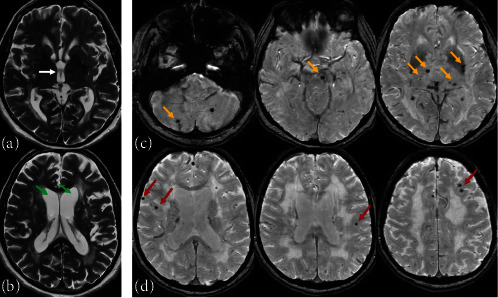

Results: The following predictors of ESUS were identified in current study: arterial hypertension (AH); increased heart rate and pulmonary arterial systolic pressure (PASP); the presence of conduction disturbance; the enlargement of left, right atrium, and left ventricle end-systolic length; increased intima-media thickness (IMT) in right and left common carotid artery (CCA); lowered Montreal Cognitive Assessment (MoСA) cognitive scale score; the presence of subcortical microbleeds; central brain atrophy; the larger size of third ventricle; and the higher medial temporal lobe atrophy (MTA) score. The following risk factors were included in the final predictive model: the presence of AH (p < 0.0005; OR = 12.98 (95% CI: 4.53-37.21)) and PASP (p=0.018; OR = 1.13 (95% CI: 1.02-1.25)) and male sex (p=0.046; OR = 2.771 (95% CI: 1.017-7.555)). The Nagelkerke's pseudo-R-squared value was 0.404 and the significance of the Hosmer-Lemeshow test was 0.733, which indicate the goodness of the final logistic regression model.